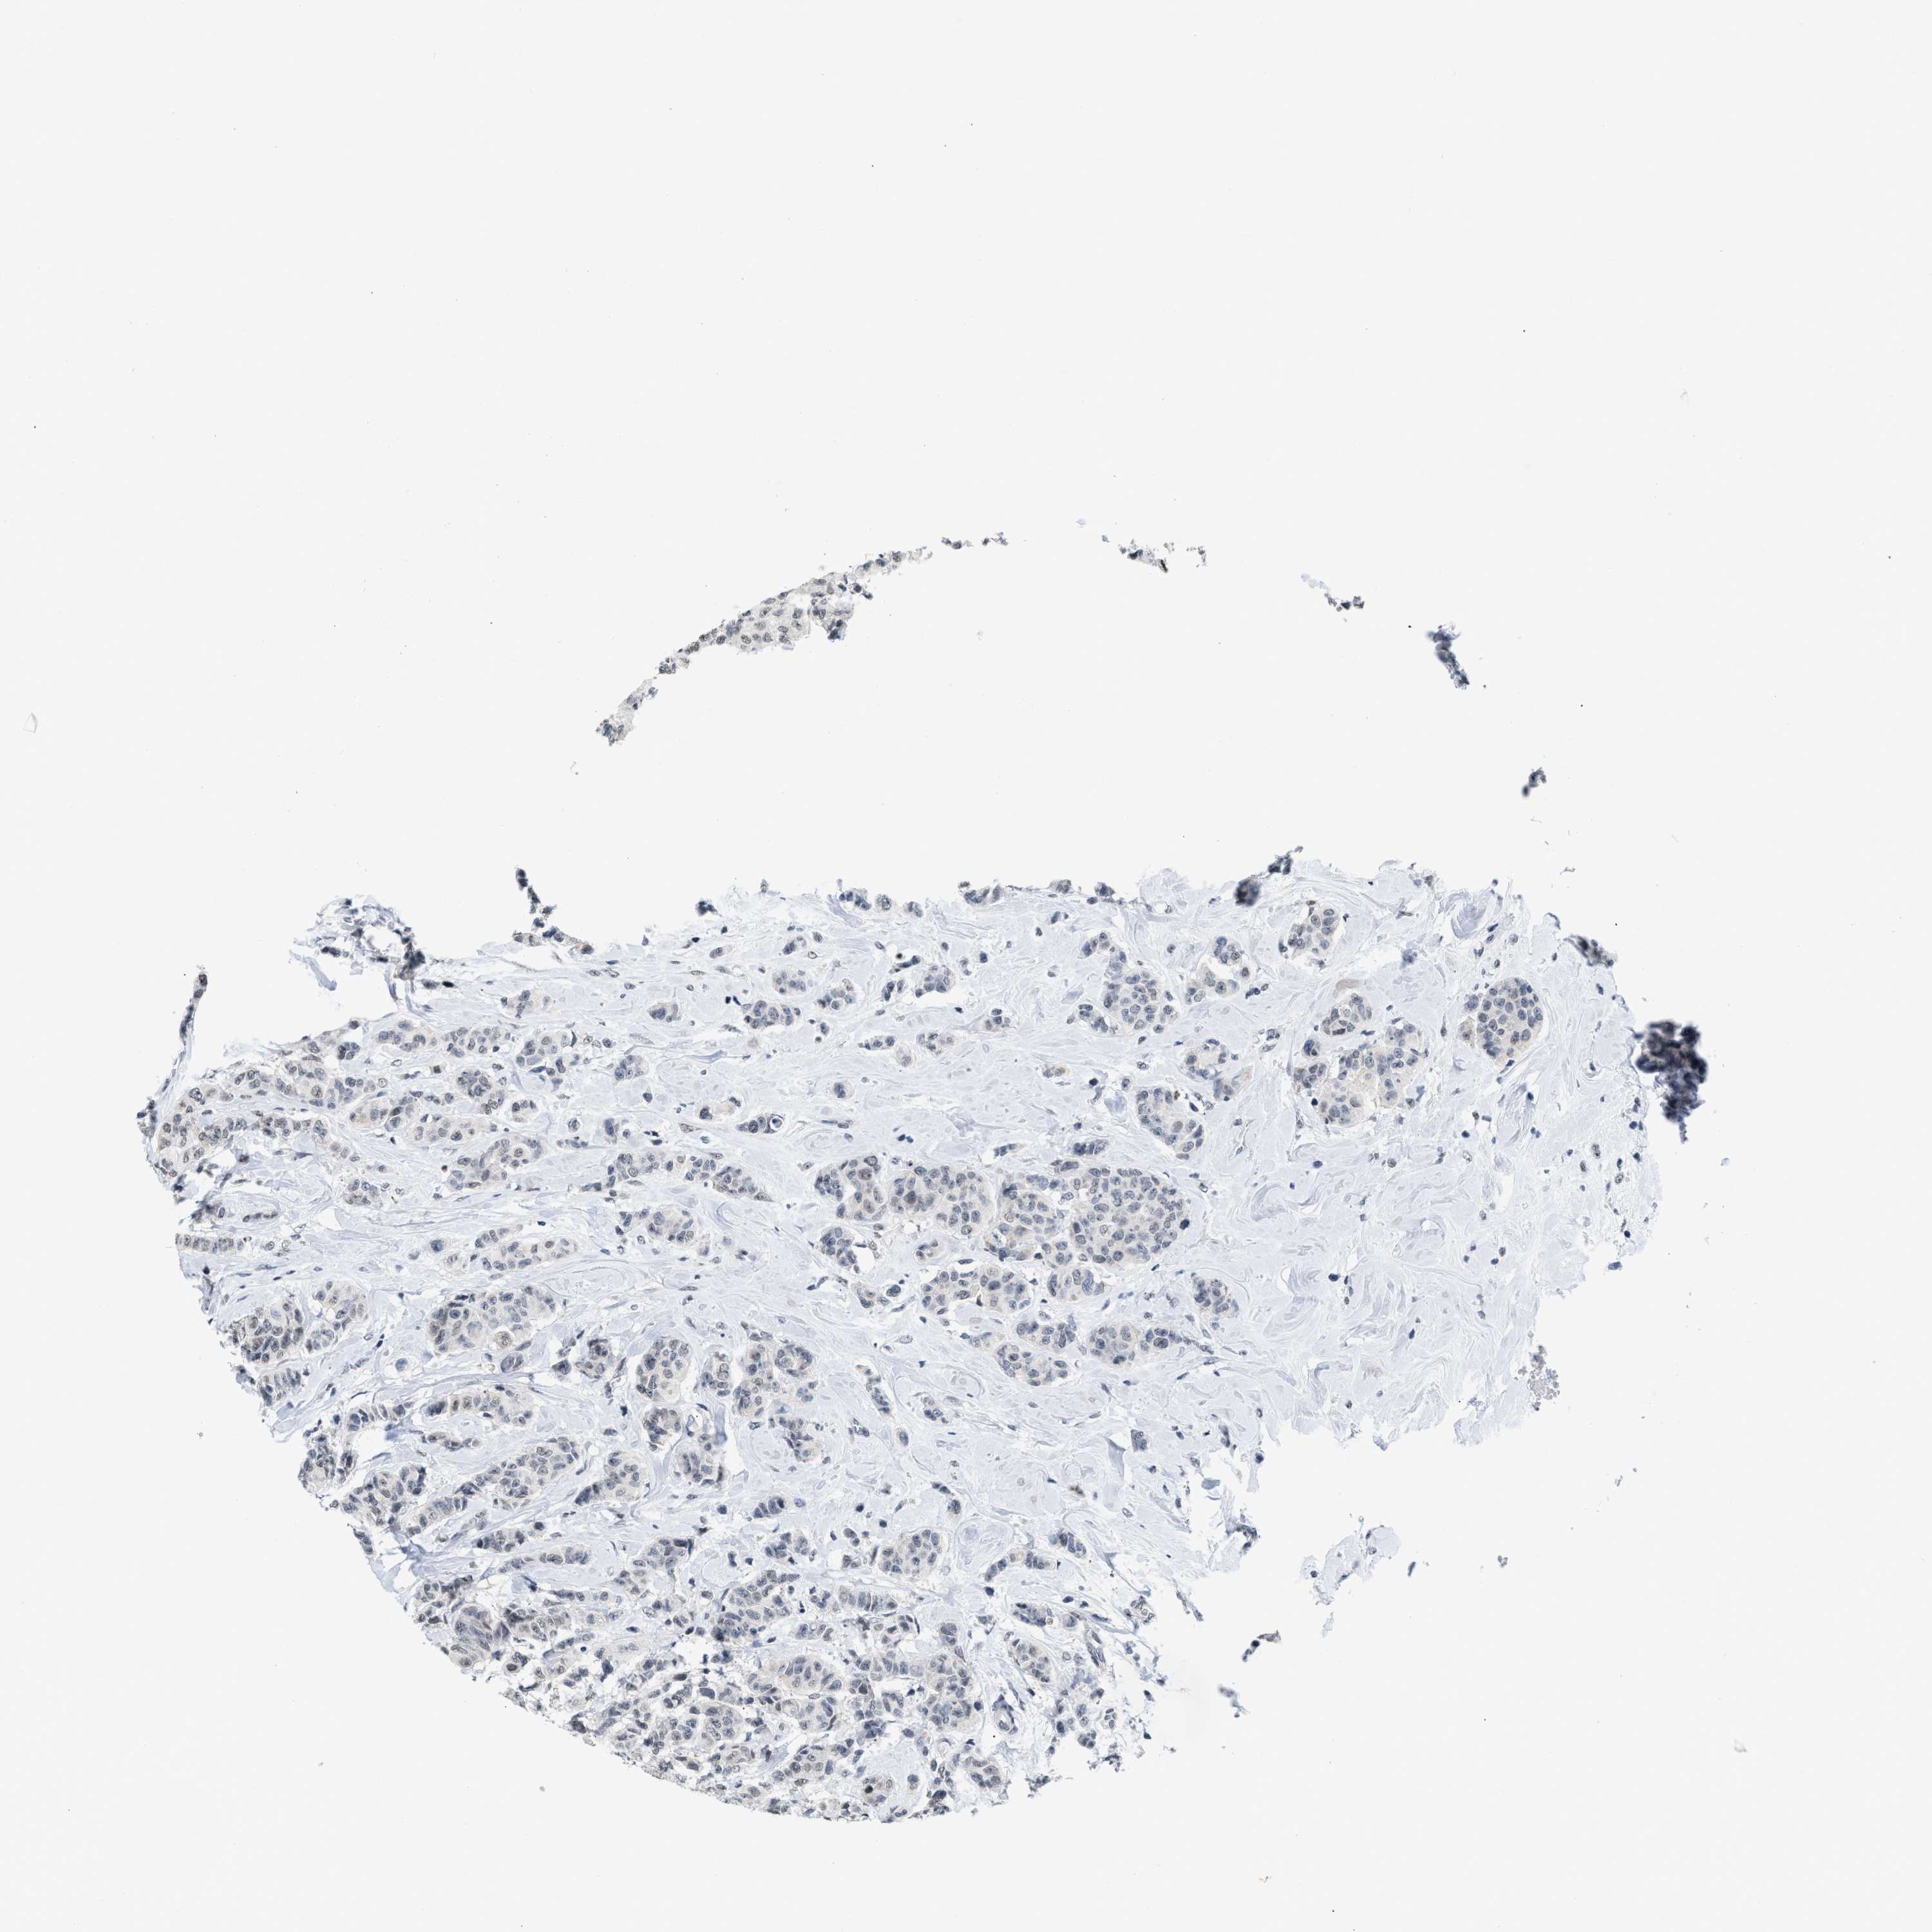

CANCER BREAST CANCER Show tissue menu

BRCA TCGA BRCA VALIDATION PROTEIN EXPRESSION

Breast cancer

Human cancer

Breast invasive carcinoma